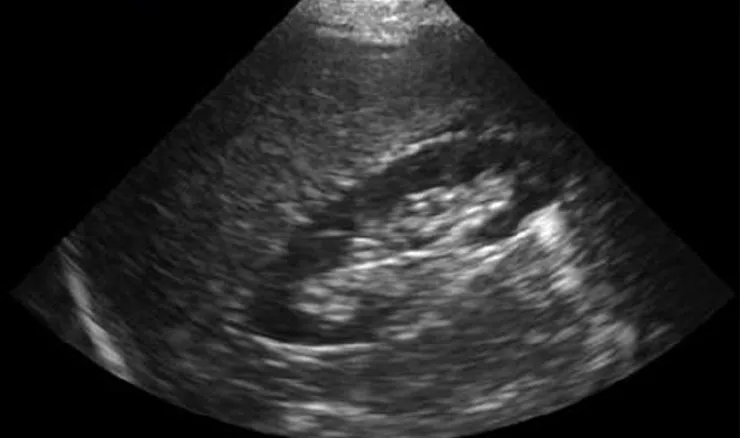

Kết quả siêu âm của bệnh nhân T.

Theo kết quả được trả trong ngày, hình ảnh siêu âm chưa phát hiện bất kỳ dấu hiệu đáng lo ngại nào. Gan, đường mật, ống mật chủ, túi mật, hay tụy, lách cùng nhiều cơ quan khác trong ổ bụng được ghi nhận bình thường.

Tuy nhiên, điều bất thường nhất khiến bệnh nhân và tất cả những ai xem kết quả siêu âm đều không khỏi ngạc nhiên đó là anh T. có "Tử cung kích thước bình thường, âm cơ đều. Buồng trứng hai bên không có gì bất thường". Bản kết quả siêu âm này đã có chữ ký của bác sĩ chuyên khoa.